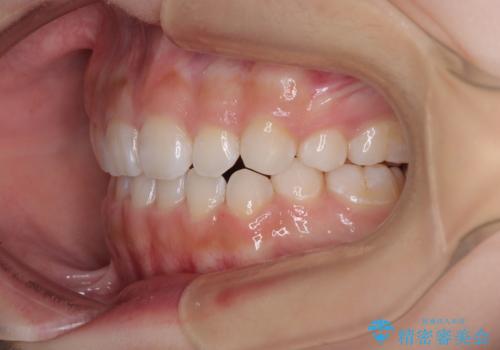

矯正治療後には、目立っていた奥歯の銀歯をオールセラミッククラウンへ作り替え、スッキリした口元に仕上がりました。